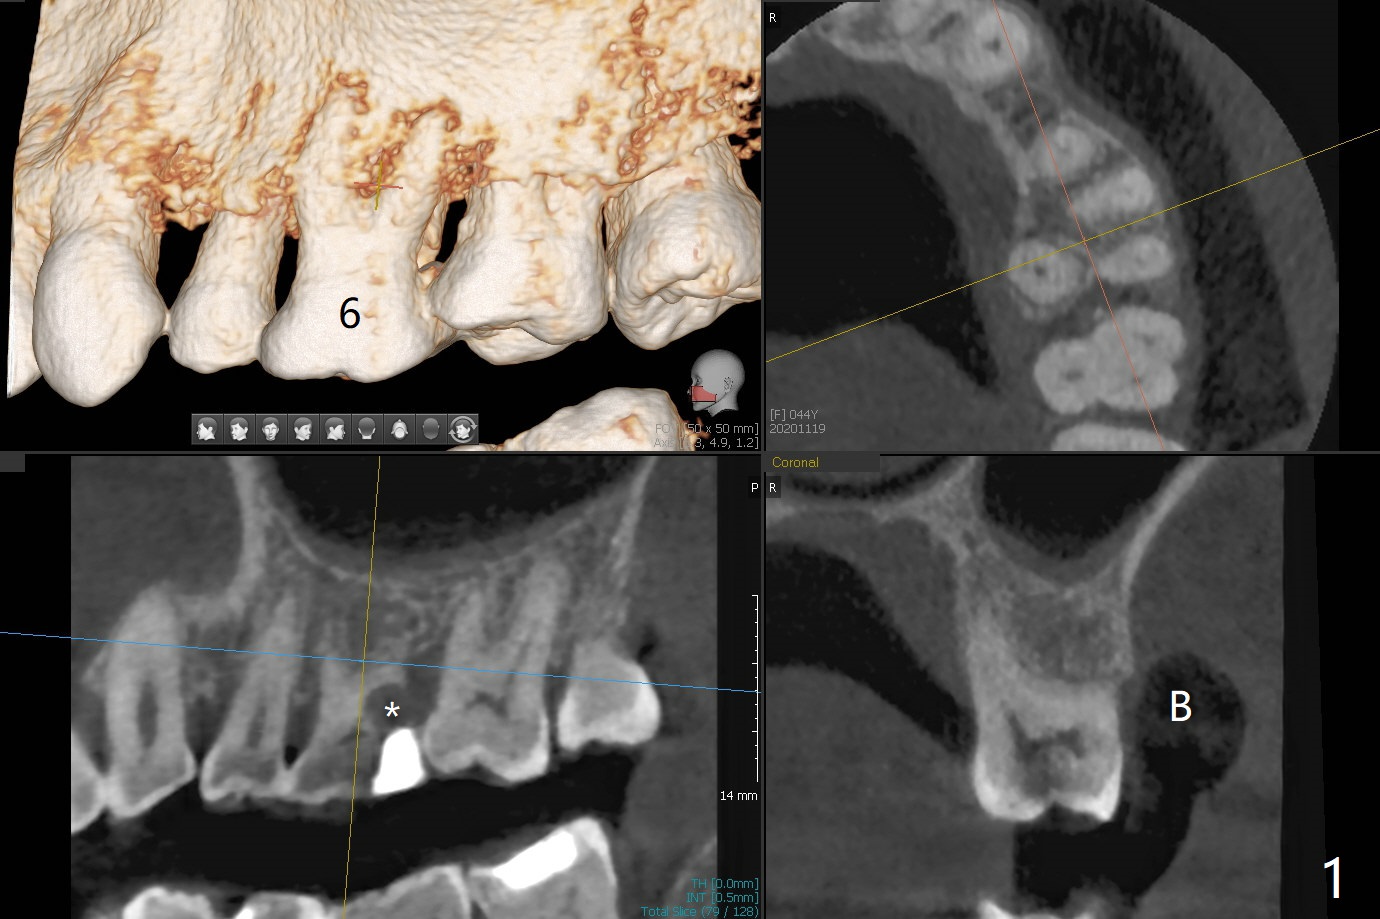

44岁女左上6远中深龋(图一:*),同意拔除种植(图二),由于近中,远中牙槽嵴不等(*),为了增加冠根比例,植体可以种浅些(箭头),但是远中多放置骨粉(红色)。为了防止钻头偏移中隔,去除牙冠(图三),保留牙根情况下,完成钻洞(图四:红色),然后拔除牙根(图五:黑色),放置植体(绿色)。